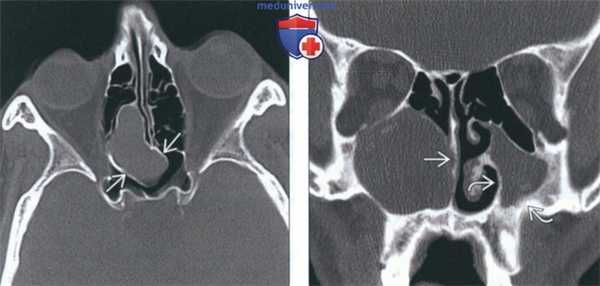

(Слева) На корональной КЛКТ (реконструкция) визуализируется буллезная нижняя носовая раковина слева. В раковину про лавирует левая верхнечелюстная пазуха; костная пластинка, отделяющая пазуху от раковины, отсутствуетвв. Буллезная раковина заполнена мягкотканным компонентом.

(Справа) На корональной КЛКТ (реконструкция) у мужчины 53 лет визуализируются буллезные верхние носовые раковины с обеих сторон. (Слева) На корональной КЛКТ (реконструкция) у мужчины 67 лет визуализируются буллезные верхние носовые раковины с обеих сторон.

2. КТ при буллезной носовой раковине:

• КТ в костном окне:

о Корональная КТ: рентгенонегативный участок в луковицеобразной части измененной раковины

3. Рекомендации по визуализации:

• Лучший метод визуализации:

о Корональная КТ в костном окне или корональная КЛКТ

(Слева) На аксиальной КЛКТ (ре конструкция) у мужчины 23 лет визуализируются буллезные нижние носовые раковины с обеих сторон.

(Справа) На аксиальной КЛКТ (реконструкция) у мужчины 23 лет визуализируются буллезные нижние носовые раковины с обеих сторон. (Слева) На корональной КЛКТ (реконструкция) у мужчины 23 лет визуализируются буллезные средние носовые раковины с обеих сторон.

(Справа) На корональной КЛКТ (реконструкция) у мужчины 23 лет визуализируются буллезные верхние и нижние носовые раковины с обеих сторон. (Слева) На корональной КЛКТ (реконструкция) визуализируются буллезные верхние носовые раковины с обеих сторон.

(Справа) На корональной КЛКТ (реконструкция) у мужчины 45 лет визуализируется буллезная левая верхняя носовая раковина.